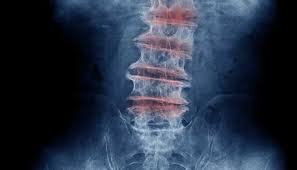

Degenerative Disc Disease Symptoms Causes Treatment